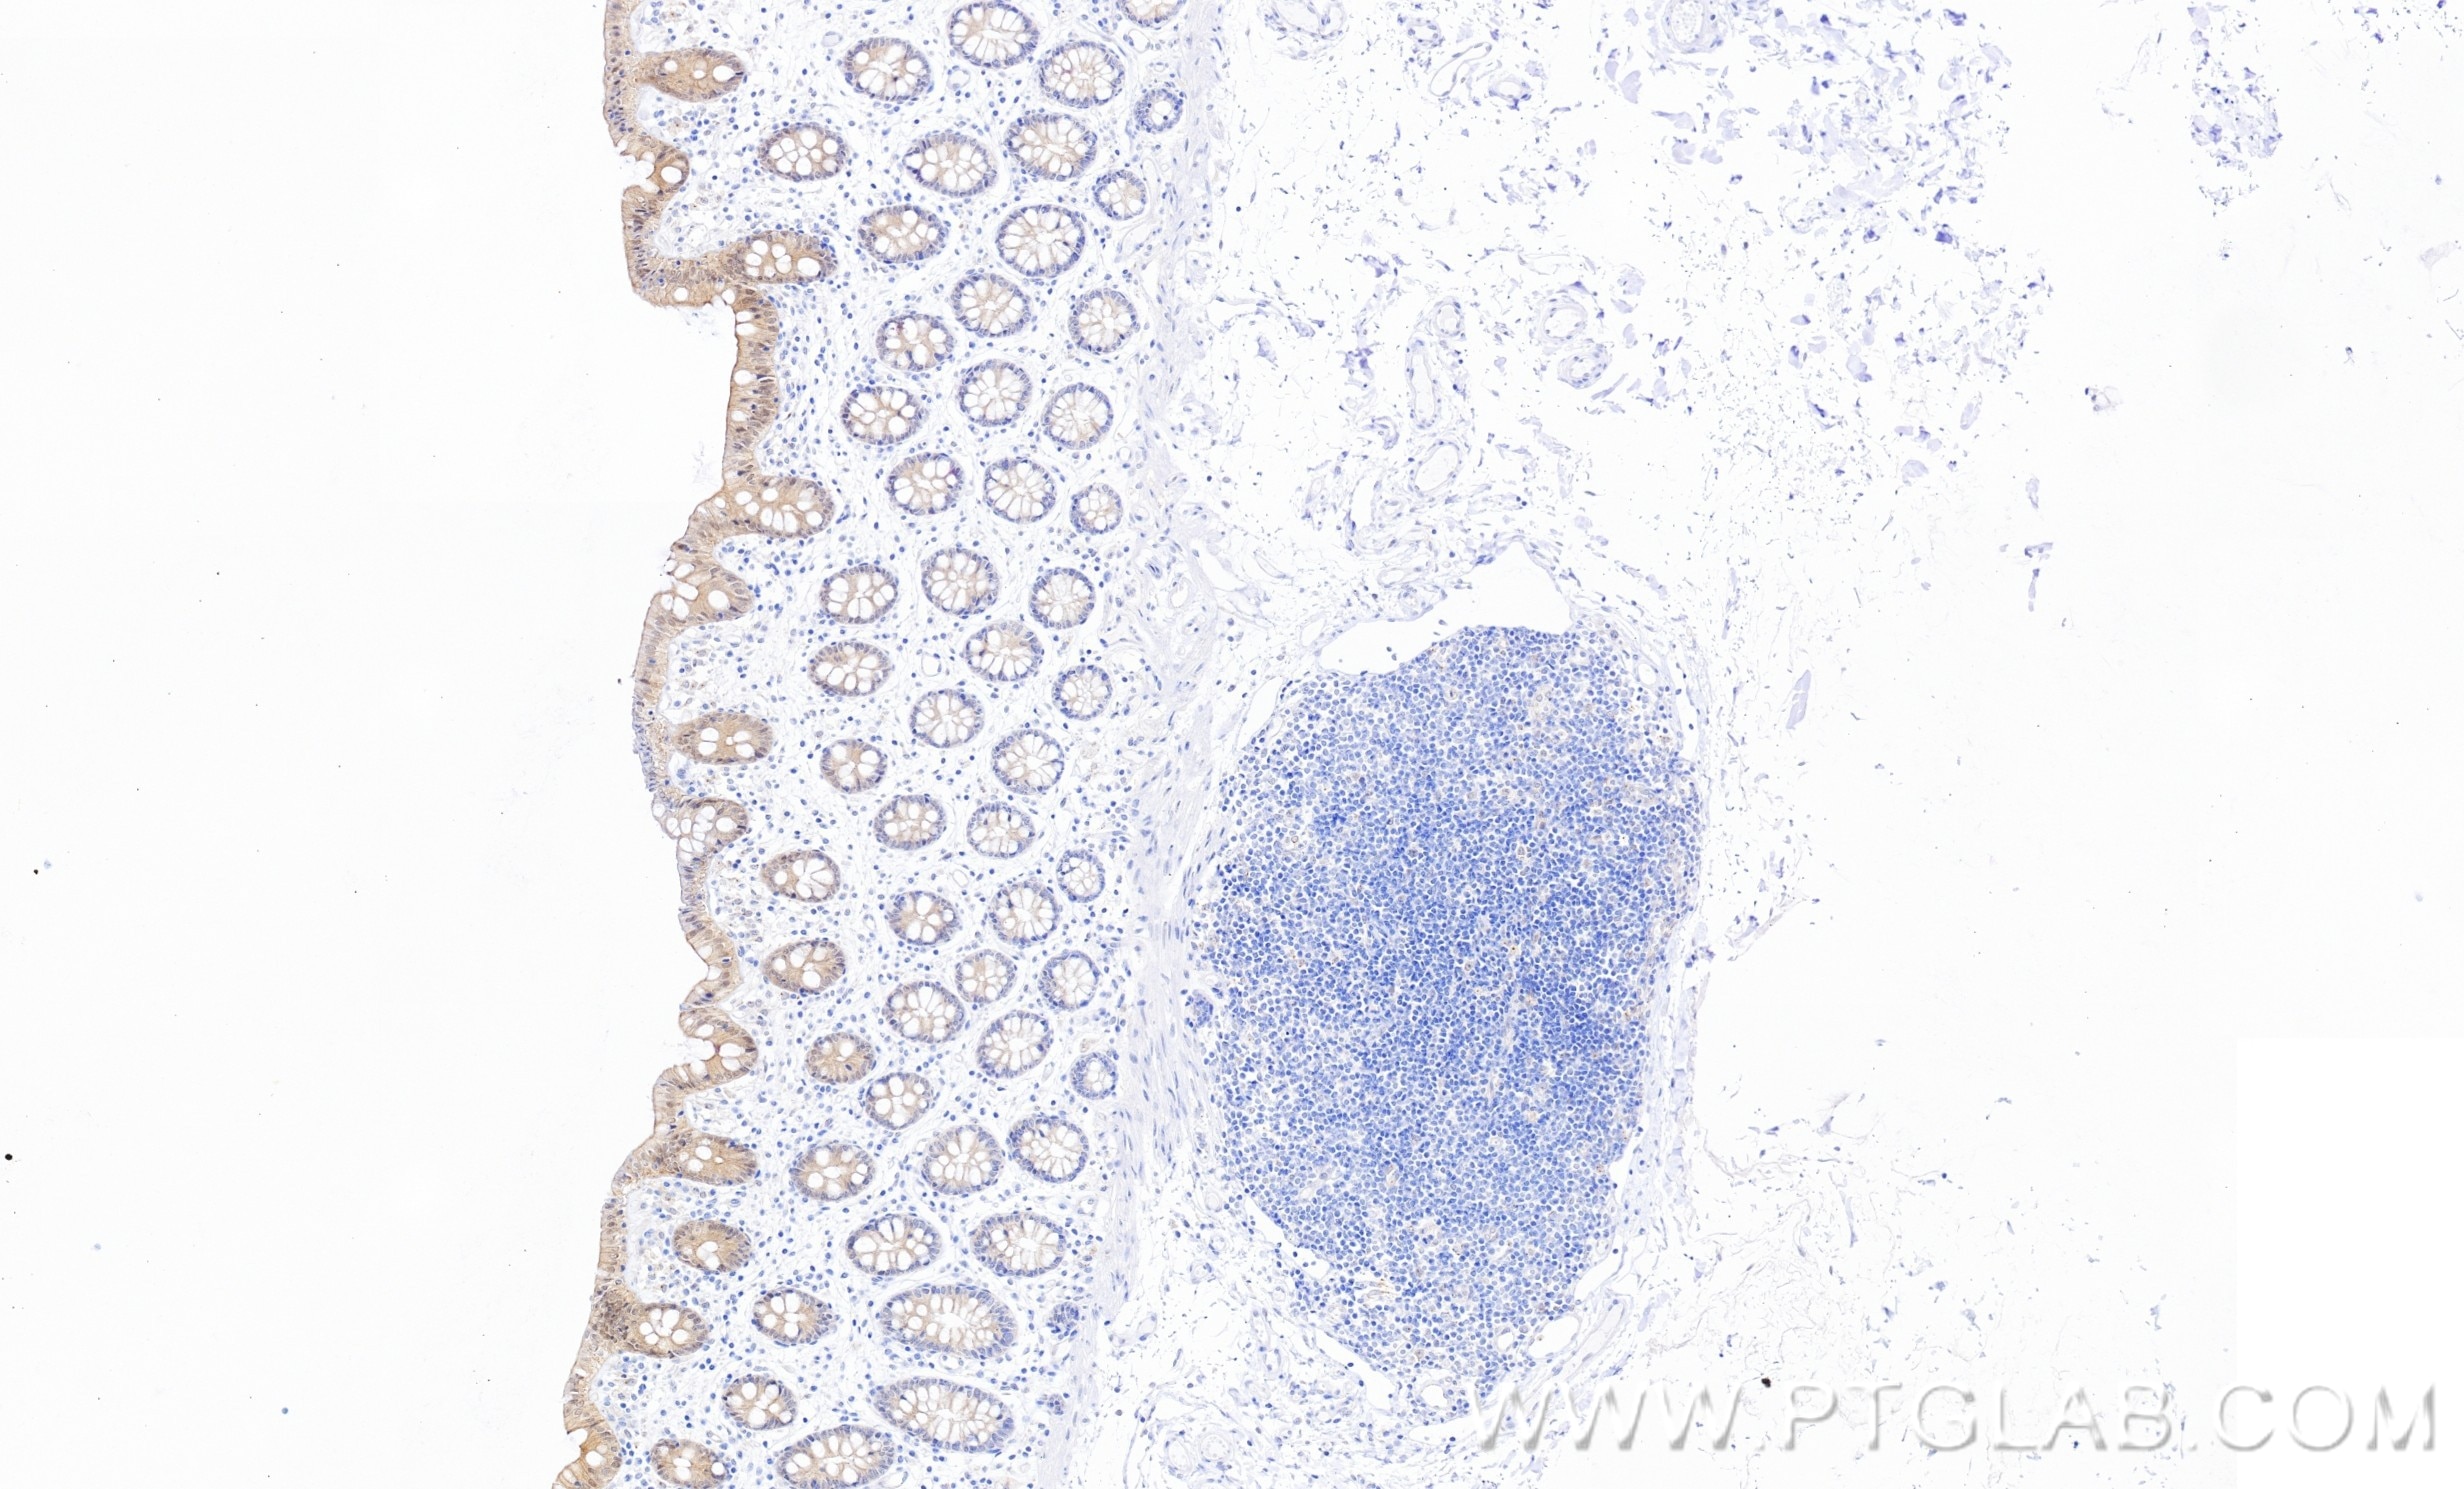

86423-2-PBS targets Casein Kinase 1 Delta in WB, IHC, Indirect ELISA applications and shows reactivity with human, mouse samples.